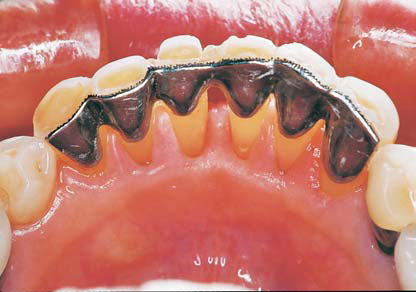

(図5)32年経過(2007年3月5日)、70歳。SPTの重要性とDiathermyの効果

■症例:歯周疾患 (図1−6)

患者:71歳、女性。

著者が大学院学生時代からの長い付き合い(33年)の患者である。Sweetが大好物で、脂質異常症と高血圧症があるため、Sugar controlを常々指導するが、なかなか習慣は変えられないようである。長年、編み物教室の教師をしており、現在も毎日出張稽古で飛び回っているようである。ハイヒールをはいて社交ダンスを2〜3時間平気でしたり、毎年海外旅行へ行かれたり、非常に活動的な患者である。一時間かけて大阪から1回/月、定期的にSPTに努めてくれている。